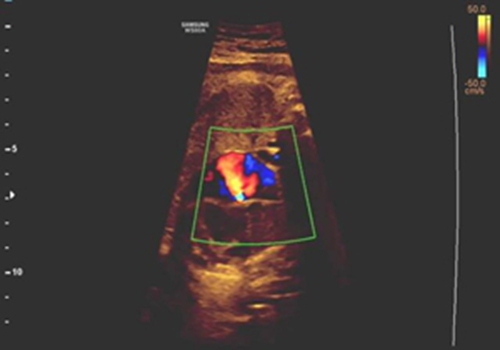

通過(guò)清晰的超聲圖像與精準(zhǔn)的血流動(dòng)力學(xué)評(píng)估,團(tuán)隊(duì)明確觀察到:胎兒卵圓孔通道無(wú)血流信號(hào)通過(guò),同時(shí)伴有右心房室明顯增大、三尖瓣大量反流等間接征象,最終精準(zhǔn)確診“胎兒卵圓孔早閉”,并準(zhǔn)確評(píng)估出心功能受損程度。